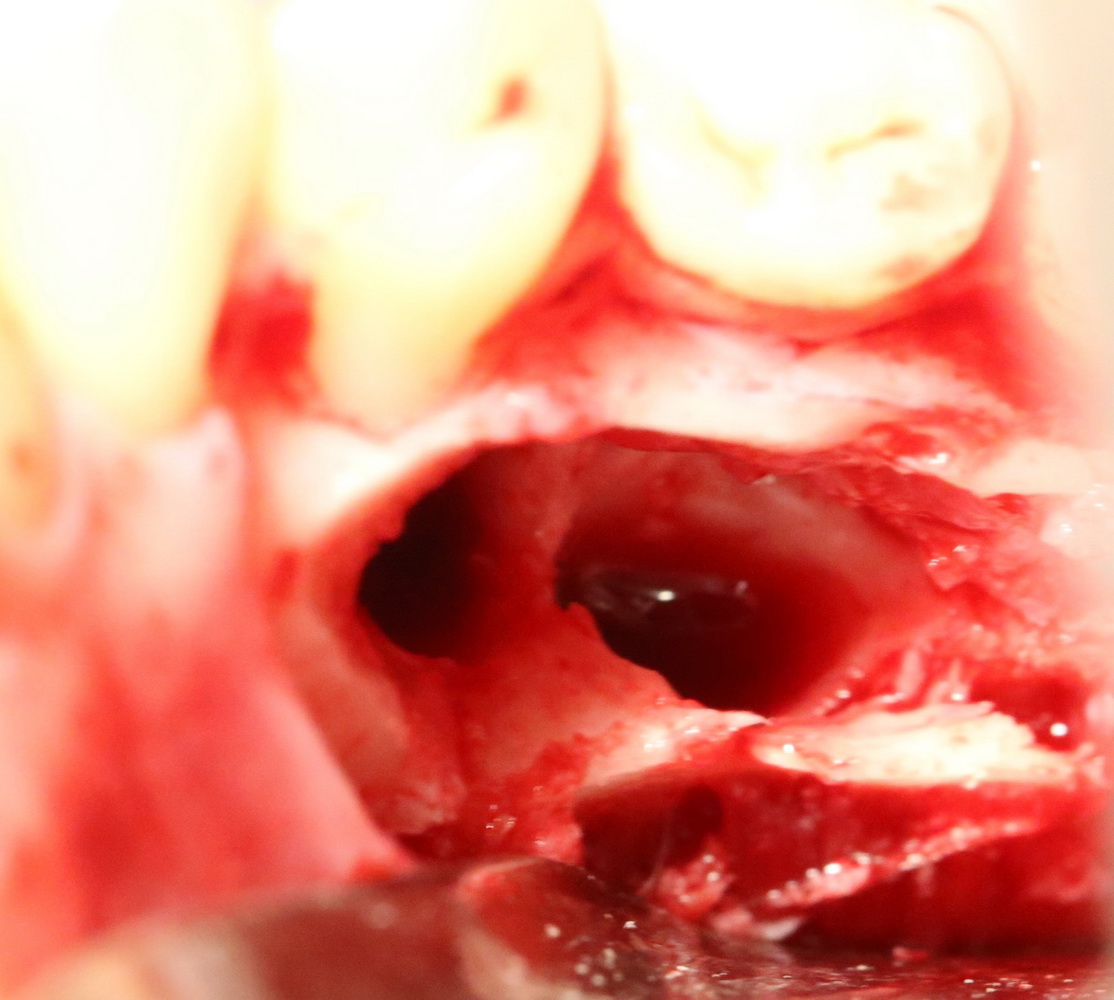

Костная «дверца» на время отделяется и убирается в физраствор, а мы видим следующее:

Это фолликулы и, частично, коронковые части сверхкомплектных зубов.

Теперь аккуратно нам нужно выделить сами зубы:

А вот они! Далее мы руководствуемся главным правилом хирурга-стоматолога:

А вот их лунки:

Теоретически, лунки можно чем-нибудь заполнить. Только чем? И для чего?

Костная ткань сама регенерирует, если ей не мешать. Поэтому не стоит толкать в лунки какой-нибудь остеопластический материал, типа Cerabone или Bioss. Нет смысла.

В данном случае я использовал обычную коллагеновую губку — и то, только для того, чтобы «костная дверца», которую я выпилил в самом начале операции, не провалилась внутрь: